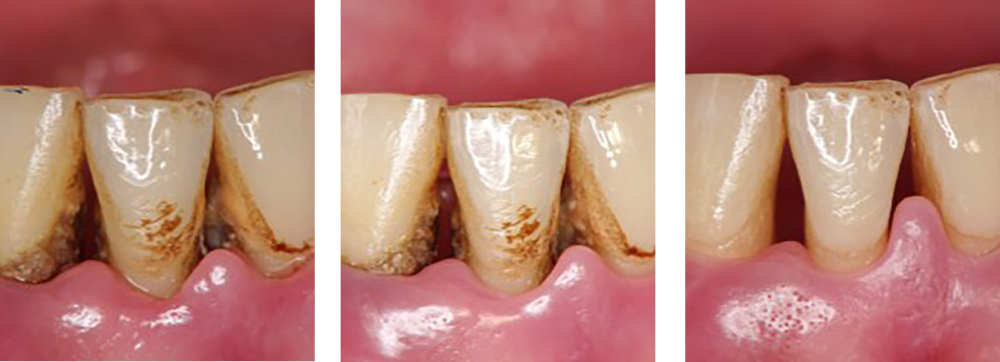

| 治療内容 | 歯磨き指導を行い、歯肉の発赤・腫脹が改善されたため歯石除去を行った |

|---|---|

| 治療期間・回数 | 1カ月・3回 |

| 費用 | 保険適用となります |

| リスク・副作用 |

|